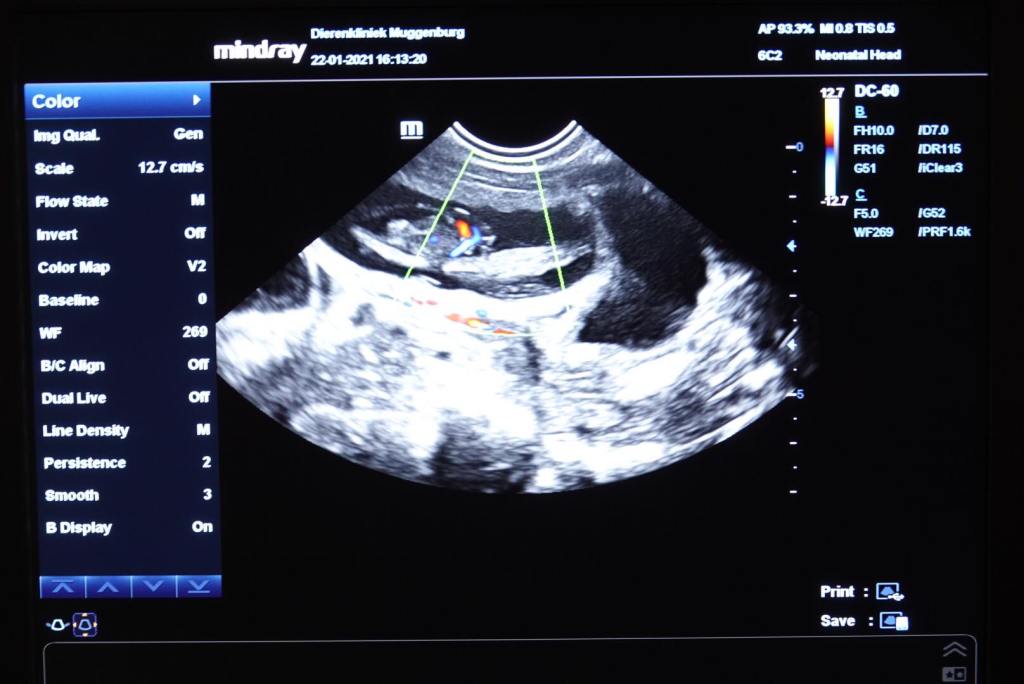

Afgelopen vrijdag waren we bij de dierenarts om een zwangerschapsecho te laten maken, op de 32e dag. Lotta had de afgelopen weken een slechte eetlust en ook dachten we veranderingen te zien aan haar tepels en buikbelijning. En toch…. zoals bij de eerdere generaties waren er twijfels of ze echt drachtig is, want het kan per slot van rekening ook gaan om een schijnzwangerschap. Lotta lag er rustig en vol vertrouwen bij in de zachte echo-goot.

Marianne en Lotta lijken hier allebei vol verwachting naar het beeldscherm te kijken ;>)

De vruchtjes kwamen al snel in beeld, inclusief hun bloedstroom in kleur. Het blijft magisch om te zien, wat daar allemaal leeft van binnen. Ze werden ook gemeten en waren op dat moment 2,5 cm groot, grote garnalen dus, die in de komende 4 weken moeten uitgroeien naar pups van zo’n 250 – 300 gram.